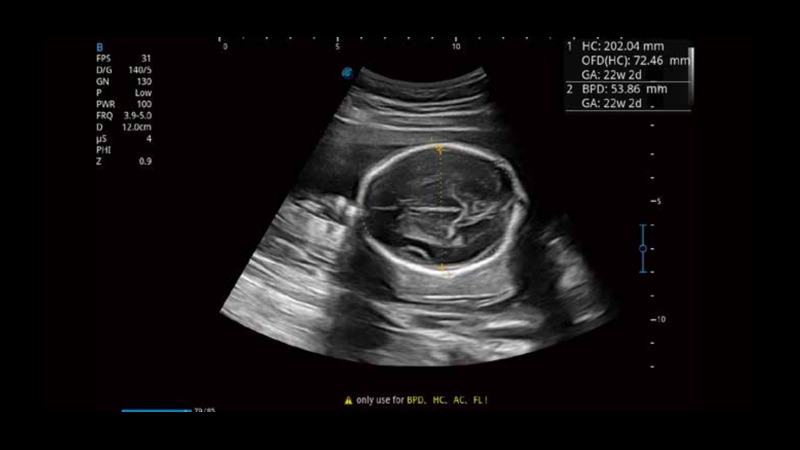

S-Fetus基于大數(shù)據(jù)深度學(xué)習(xí)算法,能夠幫助您在產(chǎn)前篩查過(guò)程中智能識(shí)別胎兒標(biāo)準(zhǔn)切面、自動(dòng)測(cè)量并錄入報(bào)告。一個(gè)按鍵,即可智能、精準(zhǔn)、高效地獲取胎兒生理指標(biāo),極大簡(jiǎn)化您的產(chǎn)科檢查操作。

可快速對(duì)產(chǎn)科掃查切面完成胎兒生理學(xué)參數(shù)的自動(dòng)測(cè)量,減少操作者按鍵次數(shù),大幅提升檢查效率。